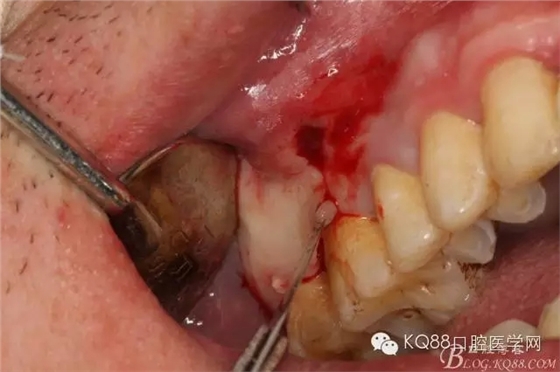

圖1.臨床檢查:16和17牙體組織正常、活力正常,其上方的前庭溝有一膿瘺,鑷子探查有大量膿性分泌物溢出。

圖7.翻全厚瓣。發(fā)現(xiàn)17牙根方的骨質(zhì)破損,破損處有大量膿性血性分泌物溢出。

圖8.繼續(xù)翻瓣至上頜結(jié)節(jié)處,發(fā)現(xiàn)骨壁缺損有花生米大小,腔隙內(nèi)有大量肉芽組織。

圖9.清理缺損骨腔內(nèi)的膿性分泌物及炎性肉芽組織,目的是找到18在哪里,隱約可以看到18白色的小樣子喲。

圖10.去除了覆蓋在18牙冠表面的肉芽組織,暴露出18的部分牙冠。

圖11.千辛萬苦,總算看到18的合面了,唯一難做的就是牙齒在里面打轉(zhuǎn)轉(zhuǎn),固定不住牙,也無法夾持住它,好郁悶。

圖12.沒辦法,只能往16旁邊去了點(diǎn)骨質(zhì)。才把18它呼喚出來。病人說他的嘴巴快被拉扯了。

圖13.取出18后,出現(xiàn)的巨大空腔,上頜竇粘膜完全破損。